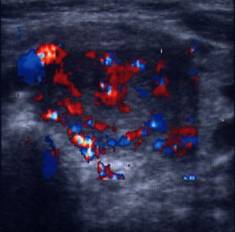

Acelasi pacient. La doppler color, vascularizatie bogata, difuza in toata

glanda

Artera tiroidiana superioara stg.

Artera tiroidiana superioara dreapta.

Acelasi

pacient. La doppler color, vascularizatie bogata, difuza in toata glanda

Examen doppler cu calcul al al velocitatii instantanee a arterelor tiroidiene

superioare.

De notat cresterea velocitatii (0,60 m/s).